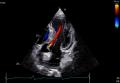

「Vivid Pioneer」は、これまで検査者が手作業で行っていた血流解析をAIが自動で行い、短時間で安定した測定プロセスを提供します。また、心臓の主要な部位(左心室と左心房)の動きや形を三次元で自動分析し、検査者間の標準化を支援します。そのほか、次世代の画像エンジン機能により、細部の見やすさ(空間分解能)や色の見やすさ(カラー感度)が向上し、より高精度な心臓の立体画像を描出します。

[画像3:

次世代の画像エンジンによる高精細な心臓画像